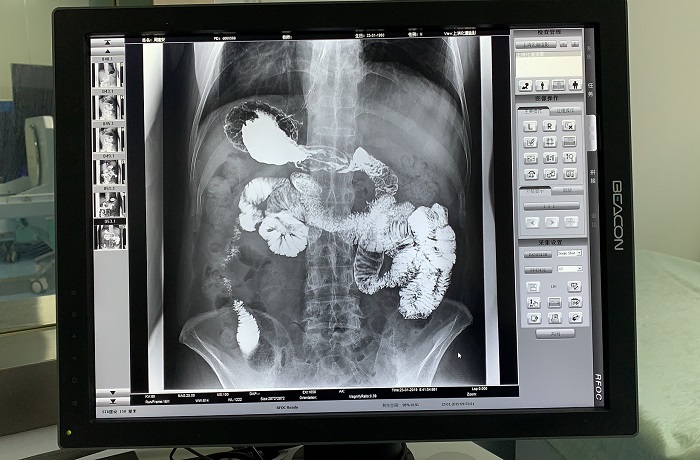

除鋇劑灌腸之外,動態(tài)DRF還適用于胃腸道造影檢查,子宮輸卵管造影等。同時,動態(tài)DRF作為普通數(shù)字X光機使用,滿足全身各部位的數(shù)字化攝影檢查需求;作為具有透視功能的胃腸機使用,滿足全身各部位的數(shù)字化透視、透視下定位、透視下穿刺、透視下點片及簡單的介入治療需求,全面適用于醫(yī)院體檢科、內科、外科、骨科、創(chuàng)傷科、急診科等多個科室臨床診斷。

胃腸道造影高清影像